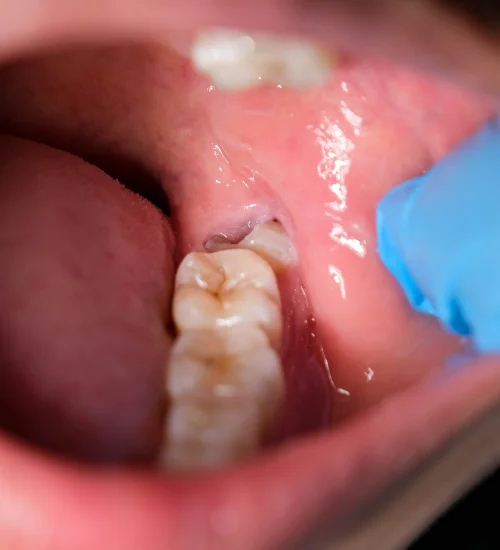

What Are Wisdom Teeth?

The last of the three molars on each side of the jaw is your wisdom tooth. They are the most likely teeth to have problems and cavities because :

- They are difficult to clean as they are right at the back, and the brush doesn’t reach there

- They are the last erupt so come out in awkward positions due to lack of space, leading to pain and infection

- They push the other teeth ahead as they erupt, leading to crowding of teeth, especially in the lower jaw.